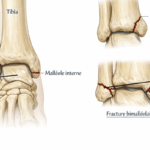

Déformations du pied

Les malpositions comme l’hallux valgus déplacent l’appui du pied et créent des zones de frottement. Ces déséquilibres favorisent l’apparition d’une bursite, notamment sur l’avant-pied ou le talon.

Un déséquilibre postural, une jambe plus courte que l’autre ou une mauvaise répartition des appuis favorisent également l’apparition de bursites.